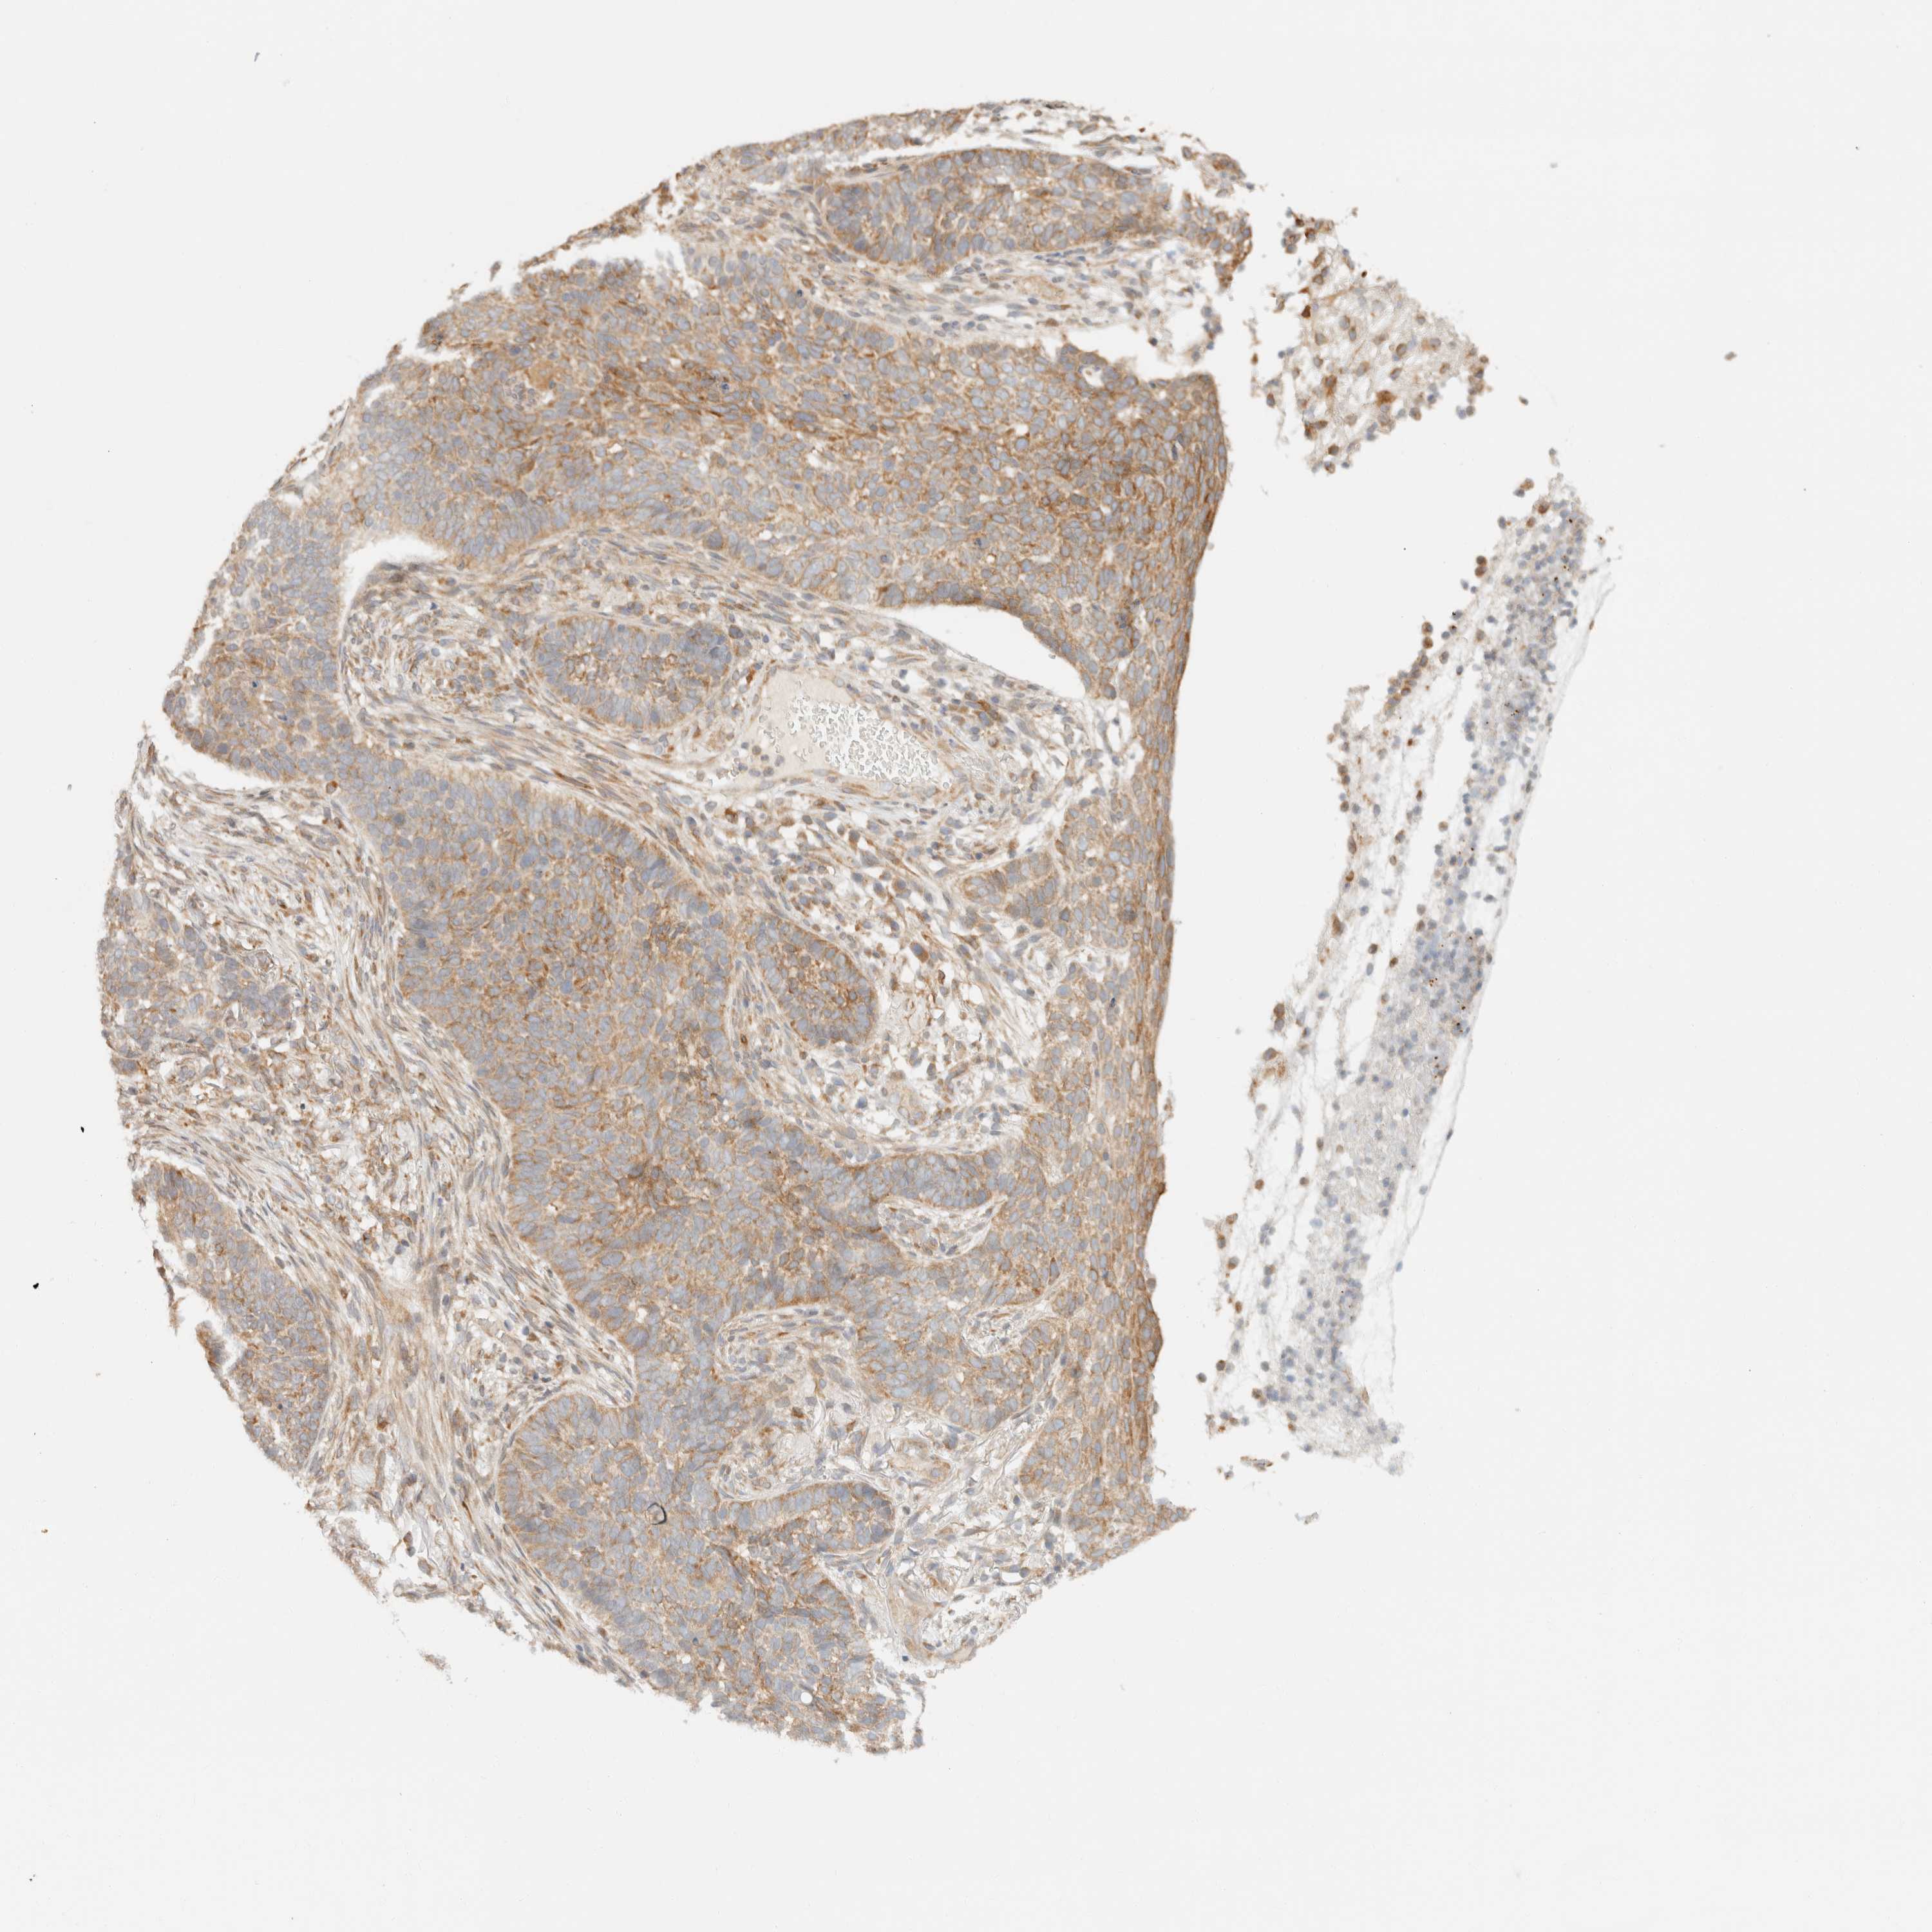

SKIN CANCER - Protein expressioni

A mouse-over function shows sample information and annotation data. Click on an image to view it in a full screen mode. Samples can be filtered based on level of antibody staining by selecting one or several of the following categories: high, medium, low and not detected. The assay and annotation is described here.

Antibody stainingi

Antibody staining in the annotated cell types in the current human tissue is reported as not detected, low, medium, or high, based on conventional immunohistochemistry profiling in selected tissues. This score is based on the combination of the staining intensity and fraction of stained cells.

Each image is clickable and will lead to virtual microscopy that enables deeper exploration of all samples and also displays staining intensity scores, fraction scores and subcellular localization as well as patient and tissue information for each sample.

Antibody HPA024702

Squamous cell carcinoma, NOS